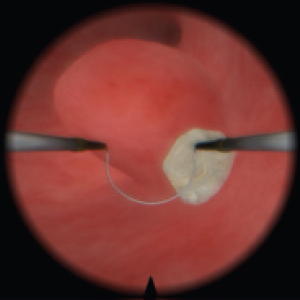

Diagnostic and surgical skills in Hysteroscopy & TUR

Resectoscope for hysteroscopy

Real resectoscope handle. Pedals for coagulation and electric dissection.

Magnetic feedback

Our proprietary magnetic feedback system allows for unprecedented immersion. Furthermore, unlike mechanical feedback systems, it is far more reliable.